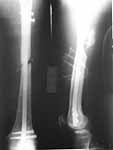

I would like to present this case to know how you would have managed this case. This young male adult was referred to us following a fall from a height. He had suffered injury to cervical spine and left femur. The previous centre could not get the distal pulses on the femoral fracture side.

At our centre: Haemodynamically stable. Grade III compound fracture left femur with a wound anteromedially in the middle thigh through which the femur had come out. Distal pulse present. Cervical spine - C1 post ring fracture right side. C2 fracture body with listhesis. No canal compromise. No neurological deficits clinically.

X rays and CT film attached. We have put the patient on skull traction and posted him for debridement and proceed ----. What we have done I would like to present after the discussion.

I did a debridement and could get a satisfactory field for internal stabilisation. The options I had kept were Ex fix, antegrade nailing and retrograde nailing. Had to be prepared for an arterial exploration if required. The vascular bundle was lying exposed through the compounding wound and could get the pulse beyond the fracture site. For this purpose I used a radioluscent flat table and did not use traction table intra-op.

After debridement I did a retrograde nailing using a solid SIGN nail. I thought this gave me the best chance to do with minimal disturbance to the head end on a flat table where the patient was supine. Sepsis to the knee was a worry but since I was using a solid nail I was fairly confident that the two area of concern( the fracture site and knee joint) will be sparated and will not spread infection from one place to other.